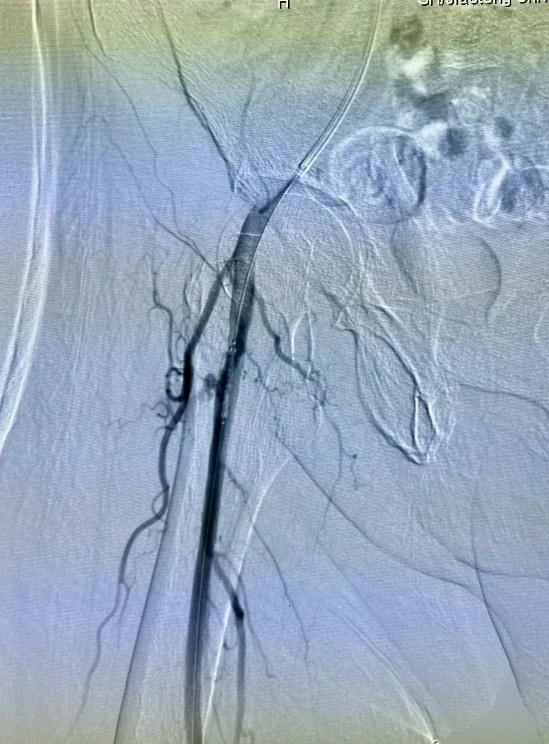

“当时患者血压都已不稳定。他的情况需要特殊支架材料。手术在医院10号楼做,材料在3号楼。但是时间就是生命,此刻大家已顾不上自己”。台风最猛烈的时候,放射介入科王忠敏医生团队一起在雨里辗转把特殊材料送到手术室,虽然穿着雨衣,但大家仍湿透全身衣服。最终,通过急诊手术为患者堵住了出血的大动脉,把患者从死亡边缘拉了回来。